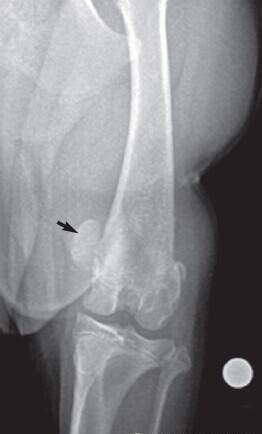

X光片正位可见髌骨位于股骨的内侧或外侧而不在滑车沟内,同时可见滑车沟变浅、胫骨近端转位和股胫关节角度异常(下图)。

X光片侧位上可见髌骨不在滑车沟内而是与股骨髁重叠(下图)。